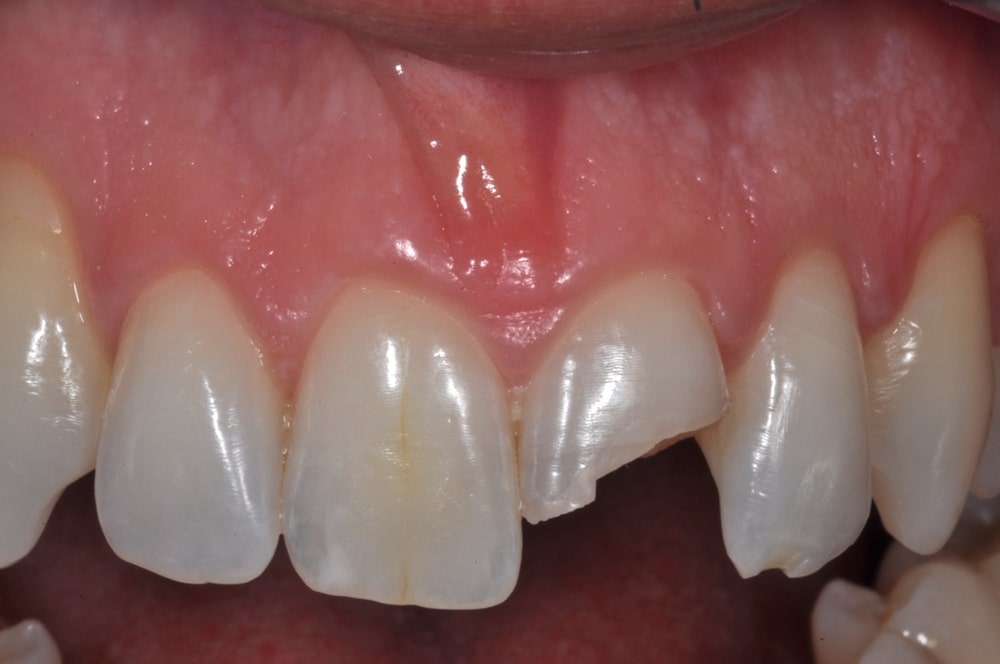

Frattura coronale

BlogEstetica e nuove tecnologie

I traumi dentali: la frattura della corona